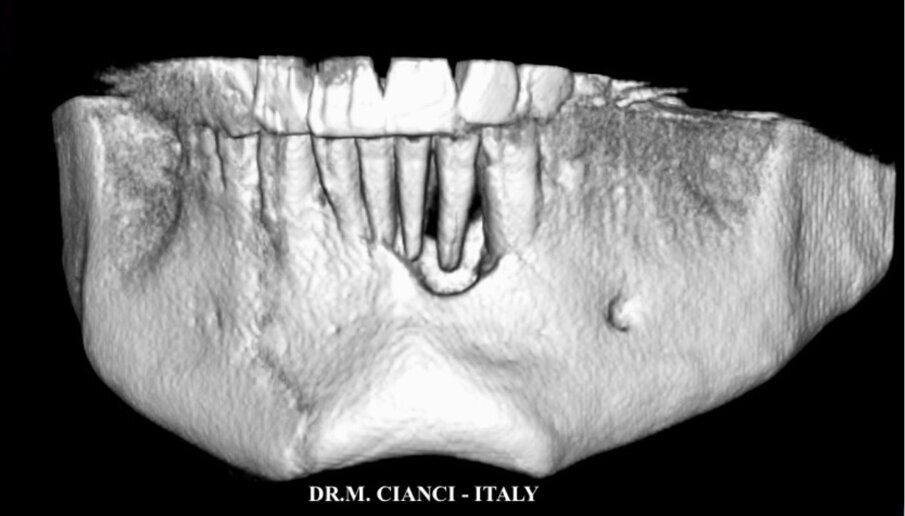

Il paziente, un uomo di 42 anni in buona salute generale e non fumatore, si presentava alla nostra osservazione presso IITS (International Implant Training School) nel febbraio 2020 lamentando difficoltà a masticare e grande mobilità in corrispondenza dei quattro incisivi inferiori (Fig. 1): l’esame TAC 3D Cone Beam evidenziava un grave riassorbimento osseo a pieno spessore da 3.2 a 4.2 con una perdita verticale di circa 14,3 mm (Fig. 2). Si decideva pertanto di procedere, una volta eseguiti tutti i trattamenti di igiene e profilassi, alla avulsione dei quattro incisivi inferiori con asportazione di ampio tessuto granulomatoso e contestuale posizionamento di un ponte provvisorio cementato tipo Maryland: un mese dopo abbiamo eseguito la rigenerazione guidata (GBR orizzontale e verticale) con innesto di materiale alloplastico di origine bovina in formato granulare (0,25-1 mm) misto a PRGF (Plasma Rich in Growth Factors), inserendo una membrana pericardica riassorbibile adeguatamente scolpita “a sella” sulla zona edentula rigenerata, riposizionando infine il lembo mucoperiosteo a ripristino della corretta anatomia del mascellare: un’ampia letteratura ha dimostrato come il plasma ricco in fattori di crescita sotto forma di concentrati piastrinici (membrane, gel e liquido) stimola e accelera la rigenerazione ossea ottenendo tempi di rigenerazione più brevi favorendo anche una guarigione più rapida dei tessuti molli2, 3 (Fig. 3).

Fig. 2 - Immagine 3D della mandibola a un mese dalle avulsioni dentarie.

Fig. 4 - Immagine 3D della mandibola post-GBR.